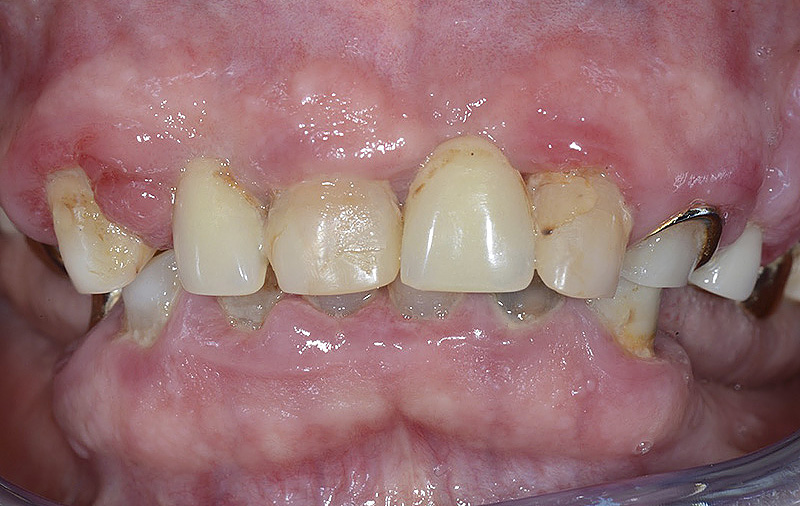

PREMESSA: in seguito all’estrazione dell’incisivo laterale superiore di destra, resasi necessaria per cause batteriche, si decide di affrontare il caso con il posizionamento di un impianto in sostituzione dell’elemento mancante dopo guarigione del sito infetto. Con tecniche rigenerative sia dei tessuti ossei mancanti a causa dell’infezione pregressa, sia dei tessuti gengivali che appaiono inizialmente troppo spostati in alto, si ripristina una corretta morfologia delle parabole (contorni) gengivali e delle papille interdentali (triangoli di gengiva tra due denti vicini).

Vengono utilizzati 2 tipi di provvisori: il primo, cementato ai denti vicini, viene utilizzato dal momento dell’estrazione del dente fino ad impianto osteointegrato (circa 6 mesi); il secondo, avvitato direttamente all’impianto, ha una funzione di prova estetica ma soprattutto di guida per la maturazione dei tessuti gengivali peri-implantari portandoli verso la maturazione completa prima di posizionare la corona finale in disilicato di litio.